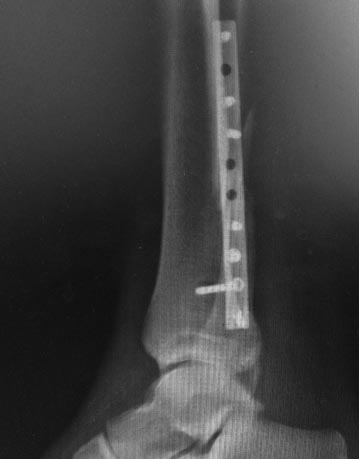

прямая проекция сейчас

до/после

Мне кажется сращение малоберцовой состоялось, межберцовый диастаз сомнителен, задний край большеберцовой клинически незначим. Укорочение малоберцовой кости не менее 3 мм.

На снимочках до и после. Если после представленный снимок сразу после операции-то там уже явный подвывих кнаружи.Причина по-моему в том, что малоберцовая кость не адаптирована полностью в сулкусе синдесмоза ,а ротирована и в таком положении стянута винтом.Так что єтап зачистки рубцов в пространстве синдесмоза обязателен.Ну и фиксация с усранением ротации малоберцовой кости 2-мя винтами.